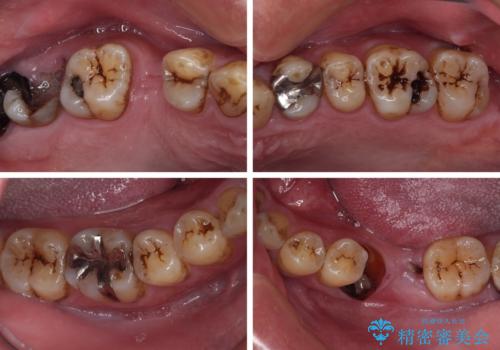

- むし歯治療途中で放置された歯が多く、スペースができたり歯が寄って来たりしているのを気にして来院された患者様です。

矯正治療を行いながら、欠損部はインプラントによる補綴治療を希望されたため、補助装置を用いたワイヤー矯正によりスペースを確保しながら歯列を整え、適宜インプラントを埋入していくこととしました。

下顎前歯にインプラントを2本埋入するのは非常に困難であり、どうしても歯肉位置に土台の金属色が見えてしまう仕上がりとなりました。無理をせずに1本のみの埋入とするか、ブリッジを提案しましたが、患者様の強い希望により、2本埋入することとなり、大変満足していただけました。